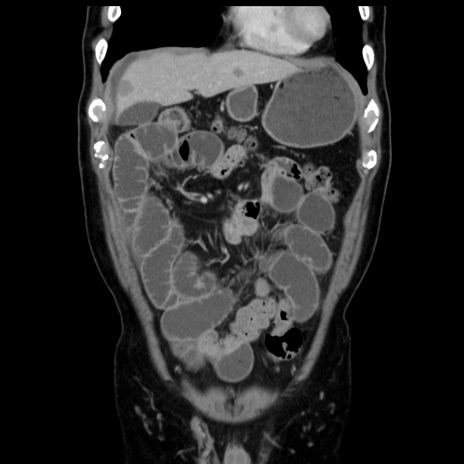

症例16(冠状断像)

【症例】 70歳代男性

【主訴】 腹痛、嘔吐

【現病歴】 約1ヶ月前より間欠的に腹痛と嘔吐あり、当院消化器内科を受診したところCTで多発する肝臓のLDAを指摘され、精査中であった。以降は消化器症状は安定していたが、2日前より嘔気と腹痛があり、同日より排便・排ガスが消失した。改善認めず、 本日、救急外来を受診した。

【既往歴】 大腸ポリープ切除後。

【身体所見】意識清明・会話良好、BT 36.3℃、BP 127/80mmHg、 P 80bpm、腹部:膨満あり、平坦・軟、上腹部正中および下腹部正中に圧痛あり、反跳痛なし、筋性防御なし。

【データ】WBC 7200、CRP 0.77